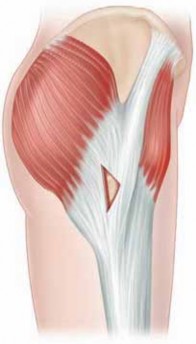

3. The iliopsoas complex, a powerful hip flexor, is formed from the psoas major and iliacus muscles (

FIG 1A

).

4. Iliotibial band (

FIG 1B

): The fascia lata covers the entire hip region, encasing its three superficial muscles, ie, the tensor fascia lata, sartorius, and gluteus maximus.

1. A confluence of the tensor fascia lata and gluteus maximus forms the iliotibial band.

2. The gluteus maximus also partly inserts into the proximal femur at the gluteal tuberosity.

3. This fibromuscular sheath was described by Henry7 as the “pelvic deltoid,” reflecting on the fashion in which it covers the hip, much as the deltoid muscle covers the shoulder.

FIG 1 • A. Depicted on the right, the proximal portion of the iliospoas has been cut away, revealing the lumbar plexus, embedded in its posterior portion. Distally, the femoral neurovascular structures are noted coursing over the iliospoas, which forms the lateral floor of the femoral triangle. On the left, the tendon is formed first from the psoas, which is then joined by the iliacus prior to its insertion on to the lesser trochanter. B. Superficial muscle layer of the hip. (A: Courtesy of J. W. Thomas Byrd, MD; B: Courtesy of Delilah Cohn.) 222